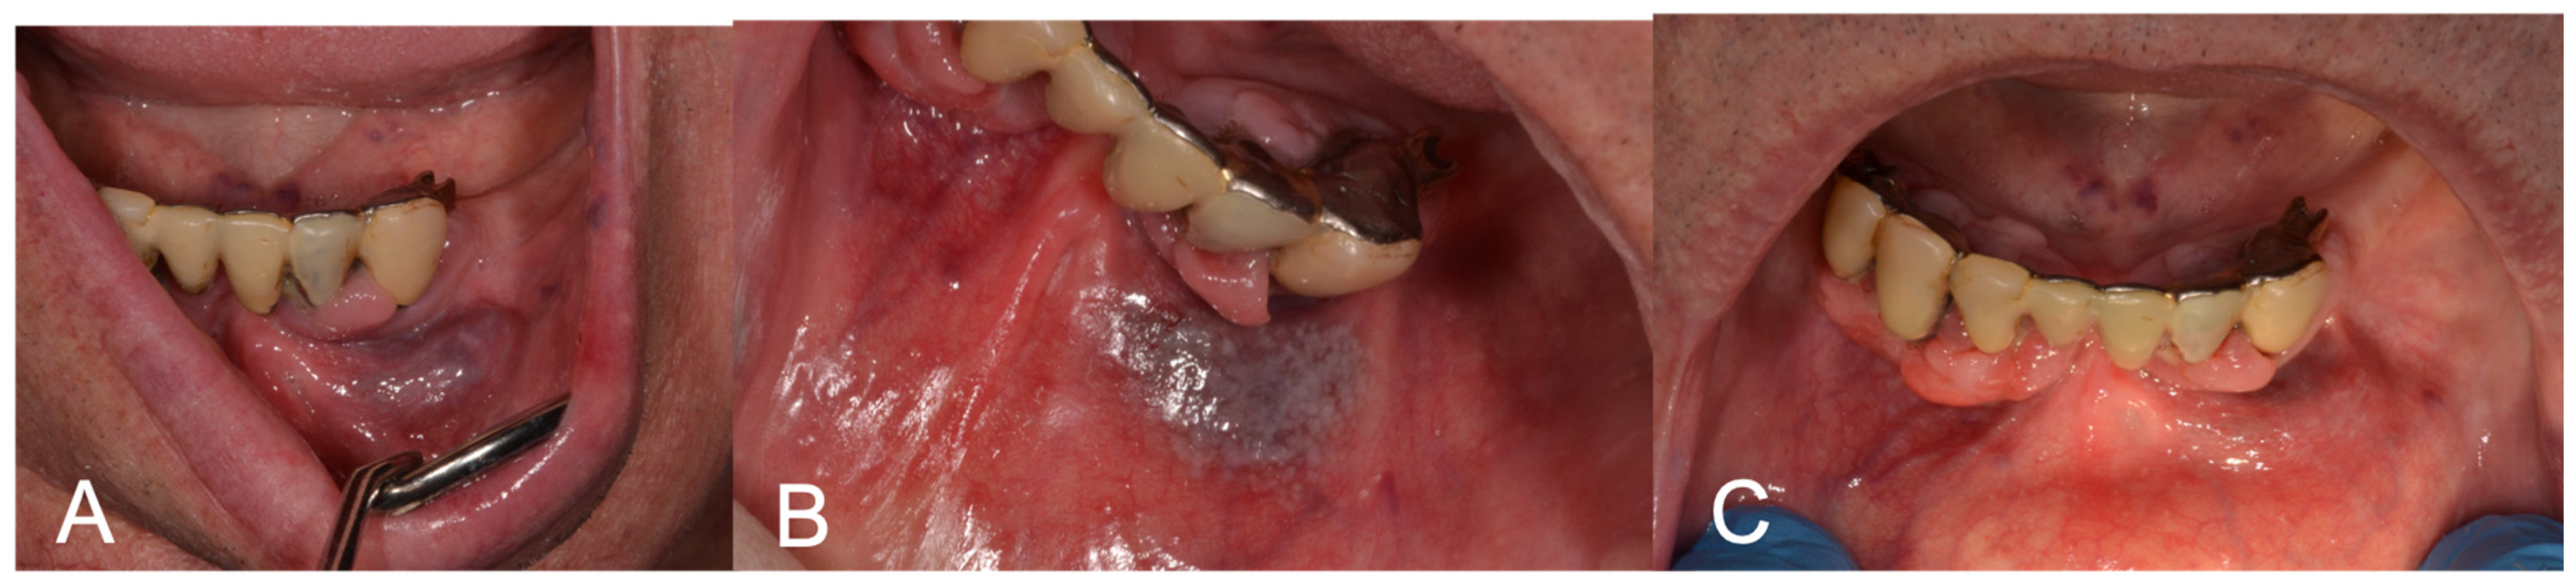

| ID | Site | Reason for Intervention | Dimension (mm) | Number of LFD Sessions | Pain | Bleeding | Scar | Side Effects |

|---|---|---|---|---|---|---|---|---|

| 1 | Lower Lip | Aesthetic | 8 | 1 | No | No | No | |

| 2 | Left Cheek | Bleeding | 10 | 1 | No | No | No | Slight tingling immediately after application |

| 3 | Lower Lip | Bleeding | 3 | 1 | No | No | No | |

| 4 | Left Cheek | Bleeding | 15 | 1 | No | No | No | |

| 5 | Tongue | Clutter | 11 | 1 | No | No | No | |

| 6 | Tongue | Clutter | 6 | 1 | Yes | No | Yes | Slight visible scar, without pain or retraction |

| 7 | Left Cheek | Bleeding | 12 | 1 | No | No | No | |

| 8 | Lower Lip | Bleeding | 20 | 1 | No | SI | No | Slight bleeding the day of the intervention |

| 9 | Left Cheek | Bleeding | 8 | 1 | No | No | No | |

| 10 | Lower Lip | Aesthetic | 8 | 1 | No | No | No | |

| 11 | Lower Lip | Clutter | 25 | 2 | No | No | No | |

| 12 | Lower Lip | Aesthetic | 3 | 1 | No | No | No | |

| 13 | Tongue dorsum | Bleeding | 3 | 1 | No | No | No | Slight tingling the day of the intervention |

| 14 | Lower Lip | Aesthetic | 10 | 1 | No | No | No | |

| 15 | Lower Lip | Aesthetic | 10 | 1 | No | No | No | |

| 16 | Lower Lip | Aesthetic | 5 | 1 | No | No | No | |

| 17 | Gingiva | Clutter | 15 | 1 | No | No | No | |

| 18 | Lower Lip | Bleeding | 10 | 1 | No | No | No | |

| 19 | Lower Lip | Aesthetic | 5 | 1 | No | No | No | |

| 20 | Lower Lip | Aesthetic | 2 | 1 | No | No | No | |

| 21 | Upper Lip | Aesthetic | 5 | 1 | No | No | No | |

| 22 | Gingiva | Bleeding | 15 | 1 | No | No | No | Ulcer after treatment |

| 23 | Lower Lip | Aesthetic | 4 | 1 | No | No | No | |

| 24 | Lower Lip | Aesthetic | 7 | 1 | No | No | No | |

| 25 | Palate | Bleeding | 8 | 1 | No | No | SI | |

| 26 | Lower Lip | Bleeding | 6 | 1 | No | No | No | |

| 27 | Tongue Dorsum | Clutter | 3 | 1 | No | No | No | |

| 28 | Lower Lip | Bleeding | 6 | 1 | No | No | No | |

| 29 | Lower Lip | Bleeding | 3 | 1 | No | No | No | |

| 30 | Lower Lip | Clutter | 4 | 1 | No | No | No |